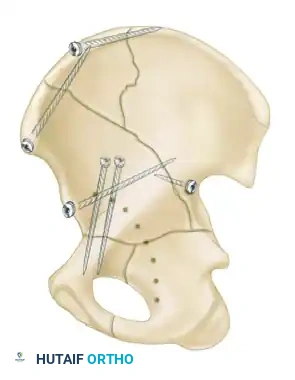

Associated fractures are complex patterns combining two or more simple fracture types. There are five associated patterns:

- Posterior Column and Posterior Wall: A posterior column fracture combined with a distinct posterior wall fragment.

- Transverse and Posterior Wall: A transverse fracture with an associated posterior wall fracture. This is a highly unstable pattern often requiring a posterior surgical approach.

- T-Shaped Fractures: A transverse fracture with an additional vertical fracture line that splits the inferior ischiopubic segment, exiting through the obturator ring.

- Anterior Column and Posterior Hemitransverse: An anterior column fracture combined with a transverse fracture through the posterior column.

- Both-Column Fractures: The most complex pattern. All articular segments are detached from the intact posterior ilium (which remains attached to the sacrum).